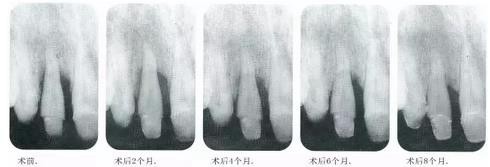

▼圖14-9~13 術(shù)后每2個月拍一次x片,檢查牙槽骨的變化??纱_認(rèn)有顯著的骨增加。